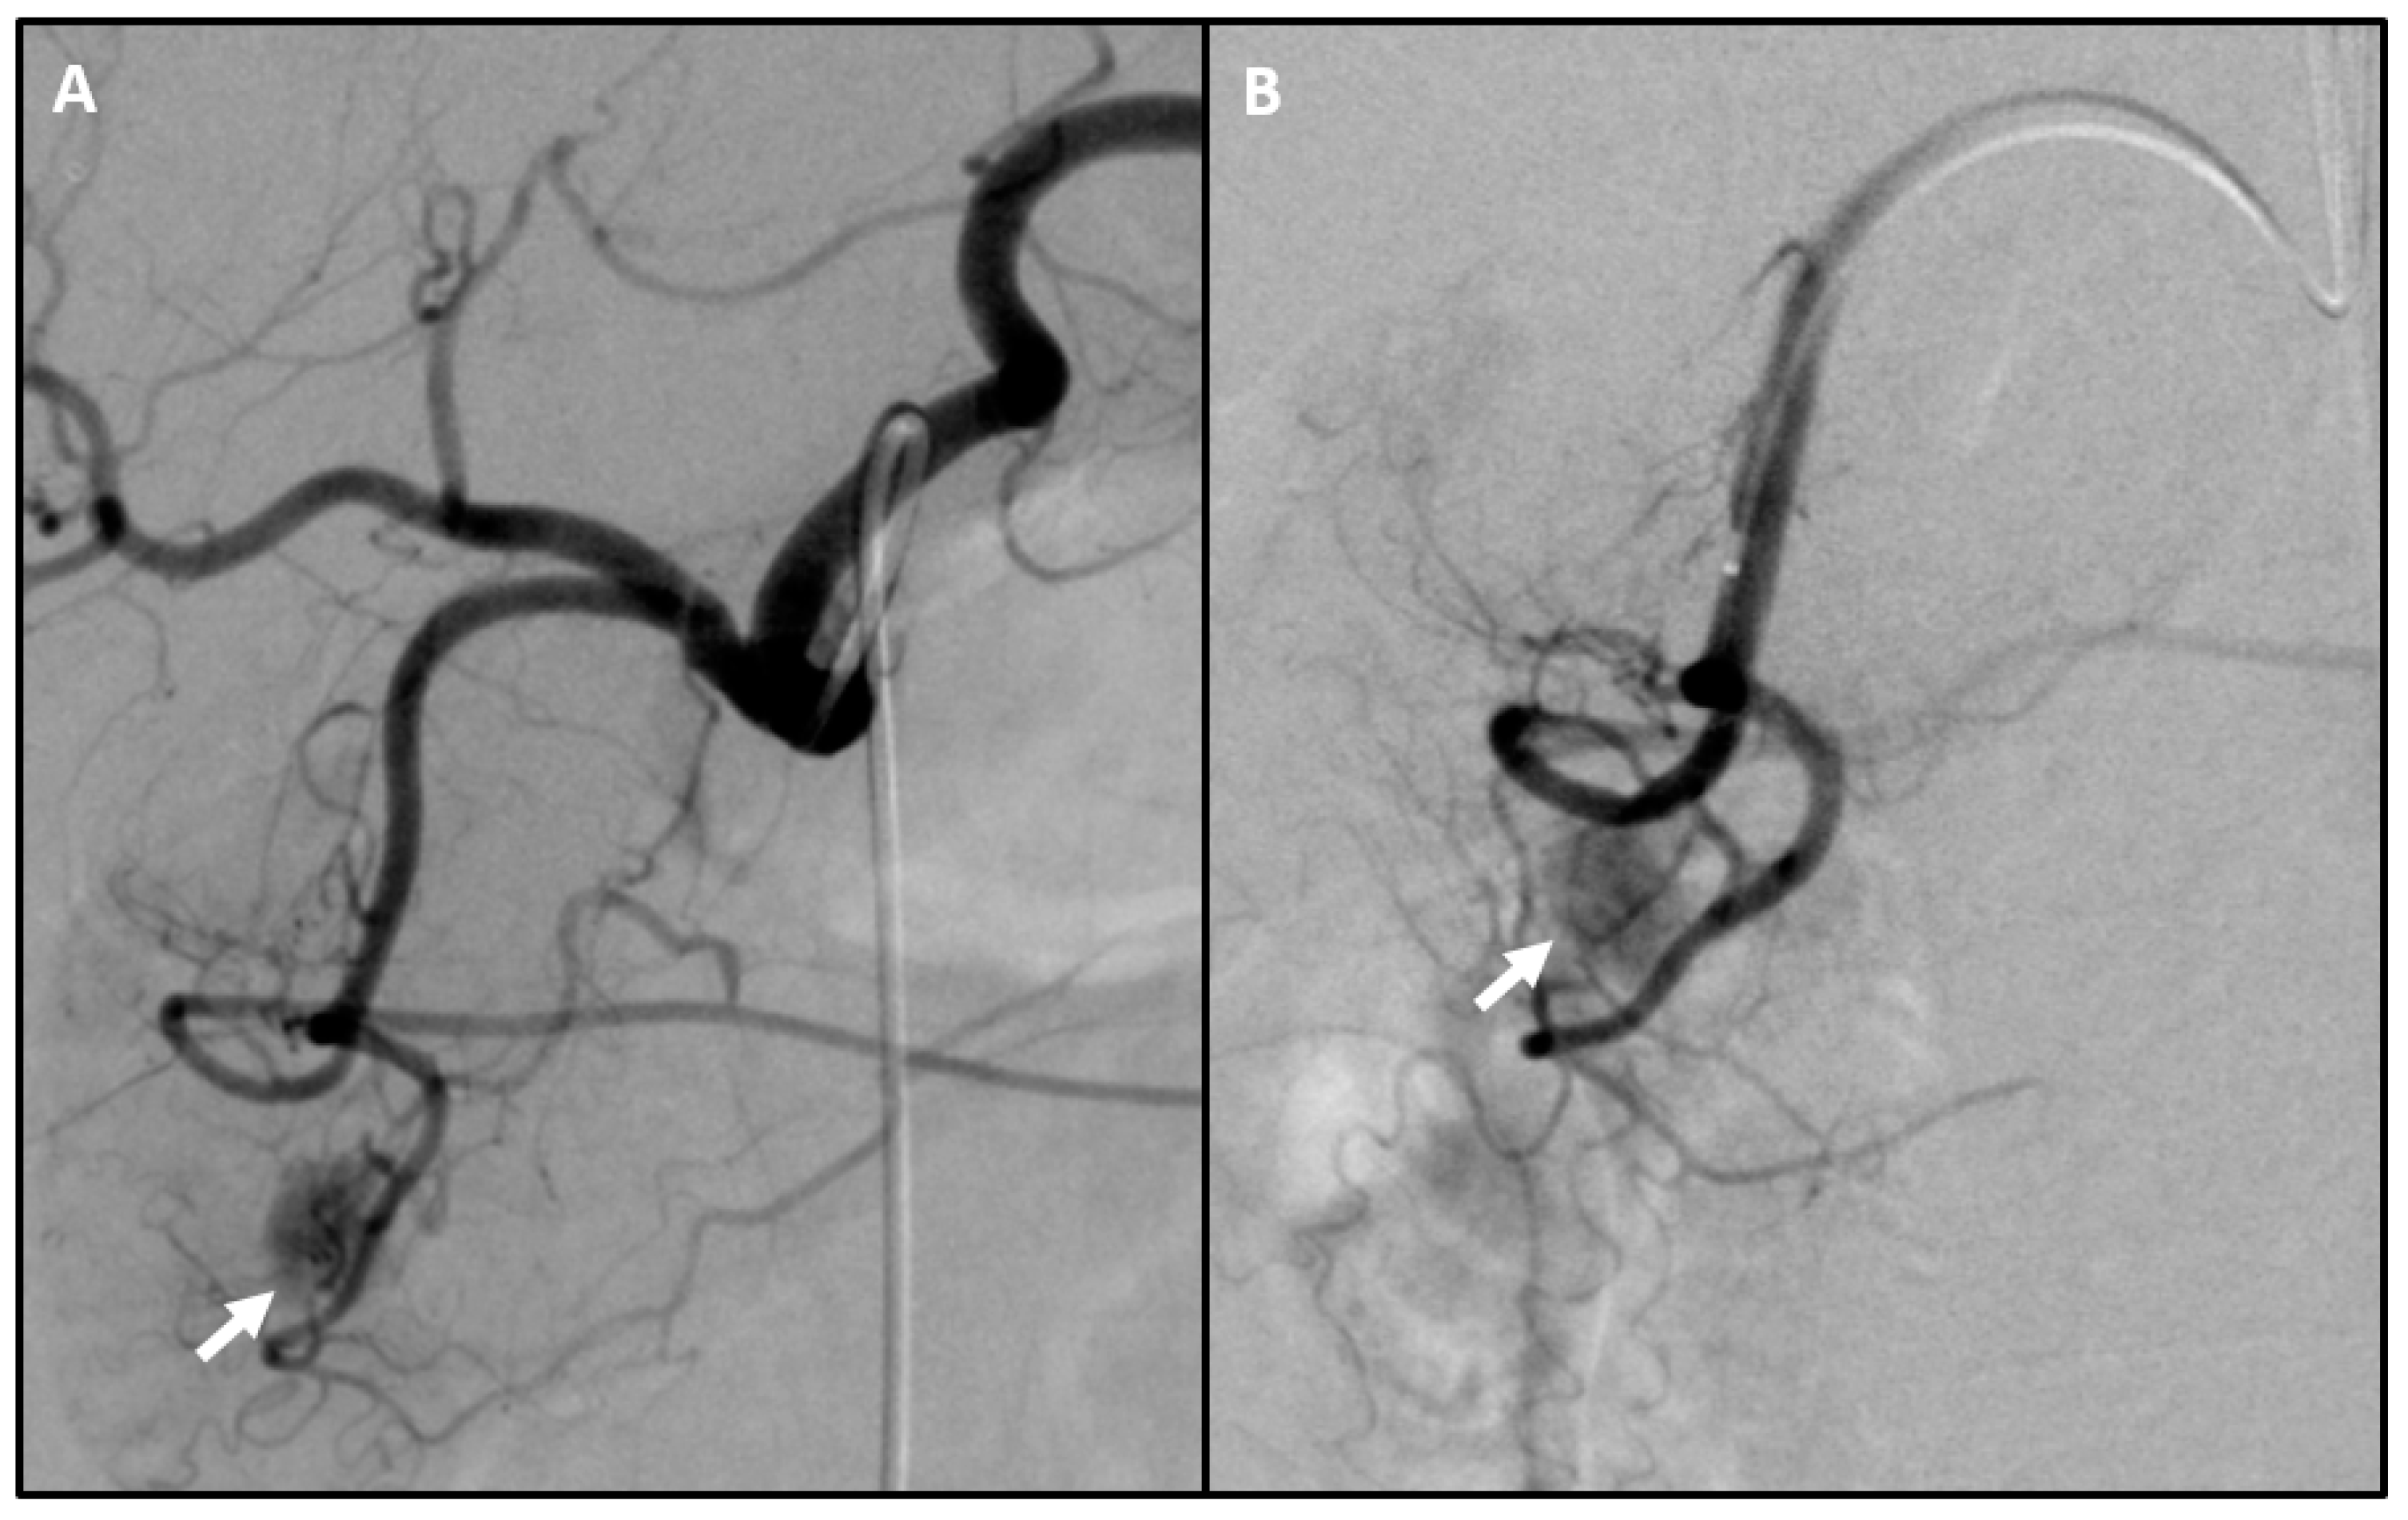

- Roche, A.; Raisonnier, A.; Gillon-Savouret, M.C. Pancreatic venous sampling and arteriography in localizing insulinomas and gastrinomas: Procedure and results in 55 cases. Radiology 1982, 145, 621–627. [Google Scholar] [CrossRef]

- Gunther, R.W.; Klose, K.J.; Ruckert, K.; Beyer, J.; Kuhn, F.P.; Klotter, H.J. Localization of small islet-cell tumors. Preoperative and intraoperative ultrasound, computed tomography, arteriography, digital subtraction angiography, and pancreatic venous sampling. Gastrointest. Radiol. 1985, 10, 145–152. [Google Scholar] [CrossRef]

- Jackson, J.E. Angiography and arterial stimulation venous sampling in the localization of pancreatic neuroendocrine tumours. Best Pract. Res. Clin. Endocrinol. Metab. 2005, 19, 229–239. [Google Scholar] [CrossRef]

- Sakuhara, Y.; Kodama, Y.; Abo, D.; Hasegawa, Y.; Shimizu, T.; Omatsu, T.; Kamishika, T.; Onodera, Y.; Terae, S.; Shirato, H. Evaluation of the vascular supply to regions of the pancreas on CT during arteriography. Abdom. Imaging 2008, 33, 563–570. [Google Scholar] [CrossRef]

- Tanaka, T.; Sakaguchi, H.; Anai, H.; Yamamoto, K.; Morimoto, K.; Nishiofuku, H.; Kichikawa, K. Catheter position for adequate intra-arterial chemotherapy for advanced pancreatic cancer: Evaluation with CT during arterial injection of contrast material. J. Vasc. Interv. Radiol. 2004, 15, 1089–1097. [Google Scholar] [CrossRef]